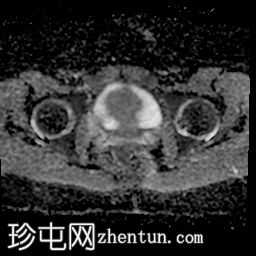

轴向

STIR

子宫体相对较小,发育良好。宫颈发育不全。

阴道整体不显影,远端可见一层细小的纤维组织,在轴向和矢状面T2加权序列上最为明显。

随后,子宫内膜和宫颈腔扩张,出现混合液体/血液降解信号(积血)。它诱发中至高T1信号,伴有依赖性低信号碎片,无病理性强化。

周围轻度盆腔积液,盆腔及附件脂肪平面模糊,信号相似,增强后强化明显。这些发现提示可能有渗漏液/血液积聚,并伴有腹膜反应。

右侧附件卵巢功能性囊肿。